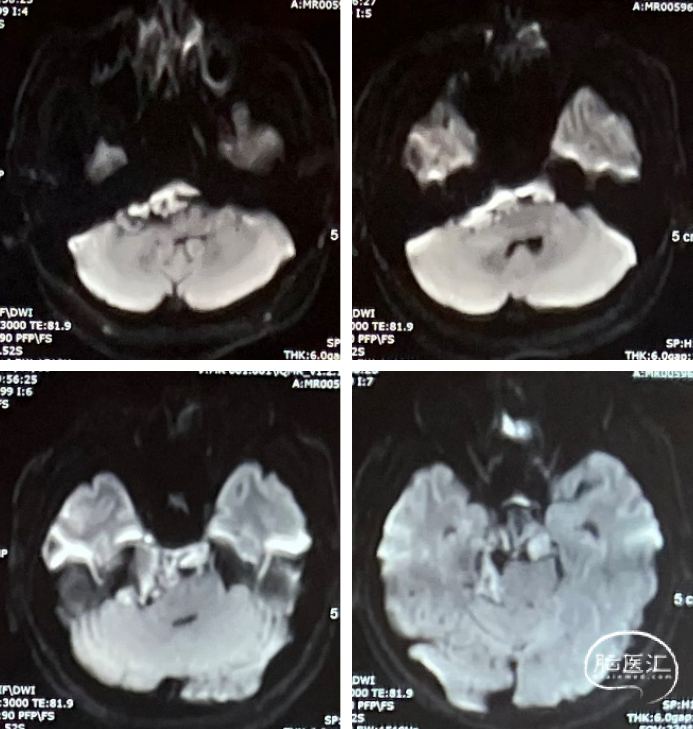

术前CT